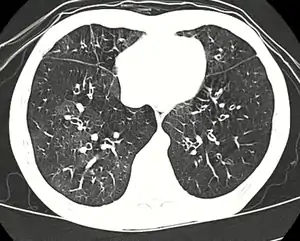

Entre as causas estão a inalação de partículas tóxicas, infeções respiratórias, doenças dos tecidos conjuntivos ou na sequência de um transplante de medula óssea ou de coração ou pulmões. Os sintomas podem só ocorrer passado duas a oito semanas da infeção ou da exposição à substância tóxica. O mecanismo subjacente consiste numa inflamação que provoca a formação de tecido de cicatrização. O diagnóstico é realizado com TAC, exames à função dos pulmões ou biópsia aos tecidos dos pulmões.[1] Em muitos casos, a radiografia torácica aparenta ser normal.[2]